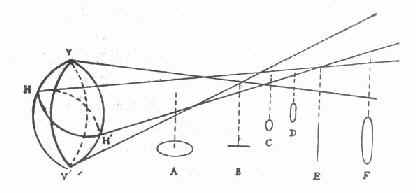

散光眼分规则与不规则两类,一般屈光学上所说的散光眼都是指前者。(图16-8)

图16-8 史氏光锥

VV′代表垂直子午线,其弯曲度大,焦距短,先成焦点。HH′代表水平子午线,其弯曲度小,焦距长,后成焦点。视网膜位于史氏光锥的A.B.C.D.E.F处时,可形成如下几种规则散光:A:复性远视散光B:单纯远视散光 C、D:混合性散光 E:单纯近视散光 F:复性近视散光